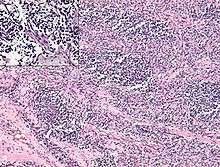

Rhabdomyosarcoma is often difficult to diagnosis due to its similarities to other cancers and varying levels of differentiation. It is loosely classified as one of the “small, round, blue-cell cancer of childhood” due to its appearance on an H&E stain. Other cancers that share this classification include neuroblastoma, Ewing sarcoma, and lymphoma, and a diagnosis of RMS requires confident elimination of these morphologically similar diseases.[22] The defining diagnostic trait for RMS is confirmation of malignant skeletal muscle differentiation with myogenesis (presenting as a plump, pink cytoplasm) under light microscopy.[1] Cross striations may or may not be present. Accurate diagnosis is usually accomplished through immunohistochemical staining for muscle-specific proteins such as myogenin, muscle-specific actin, desmin, D-myosin, and myoD1.[28][29][30] Myogenin, in particular, has been shown to be highly specific to RMS,[31] although the diagnostic significance of each protein marker may vary depending on the type and location of the malignant cells. The alveolar type of RMS tends to have stronger muscle-specific protein staining. Electron microscopy may also aid in diagnosis, with the presence of actin and myosin or Z bands pointing to a positive diagnosis of RMS.[1][29] Classification into types and subtypes is accomplished through further analysis of cellular morphology (alveolar spacings, presence of cambium layer, aneuploidy, etc.) as well as genetic sequencing of tumor cells. Some genetic markers, such as the PAX3-FKHR fusion gene expression in alveolar RMS, can aid in diagnosis. Open biopsy is usually required to obtain sufficient tissue for accurate diagnosis. All findings must be considered in context, as no one trait is a definitive indicator for RMS.